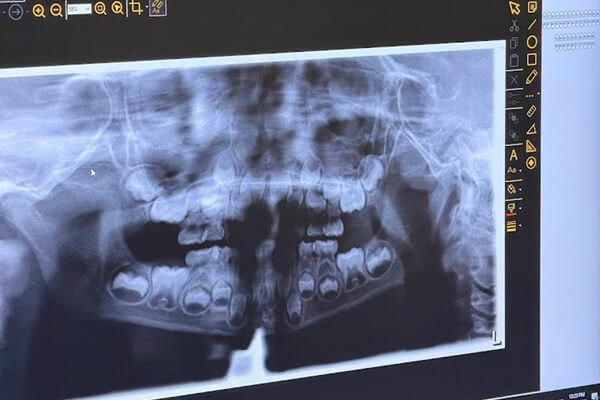

Digital X-rays allow us to see areas of the mouth that cannot be evaluated during a visual exam alone. Many dental concerns develop quietly beneath the surface, making imaging an important part of preventive and diagnostic care.

Cavities between teeth

Infection or abscesses

Bone changes around teeth

Impacted or developing teeth

Concerns before symptoms appear